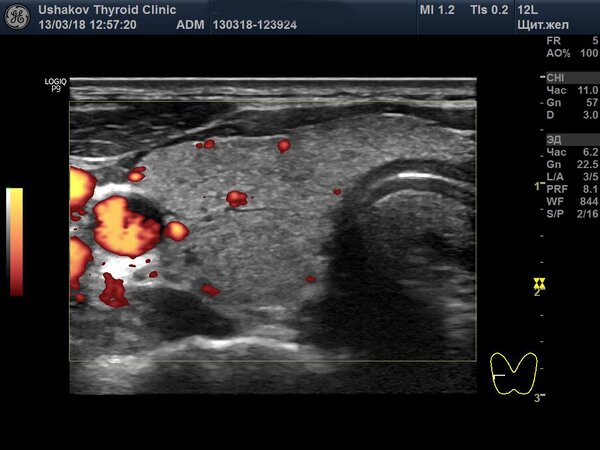

На этой неделе в нашей клинике был проведен осмотр пациентки, которая в 2001 году, в возрасте 13 лет, перенесла обширную операцию на щитовидной железе — так называемую 90% субтотальную субфасциальную резекцию. Это означает, что хирурги удалили почти всю ткань органа. Спустя 17 лет, во время ультразвукового исследования, мы с удивлением обнаружили, что все анатомические части щитовидной железы полностью восстановились, и визуальных признаков проведенной операции практически не осталось. Единственным напоминанием о хирургическом вмешательстве был тонкий, едва заметный рубец на коже.

Как же стало возможным такое полное восстановление? Во время операции хирург оставил примерно 10% ткани железы, преимущественно в тех областях, где проходят важные кровеносные сосуды и нервы. Пациентка в послеоперационный период не принимала заместительную гормональную терапию. Оставшаяся ткань, благодаря активной стимуляции со стороны нервной системы, запустила мощные процессы регенерации. В результате щитовидная железа не только восстановила свой первоначальный объем, но и полностью вернула свою анатомическую форму.